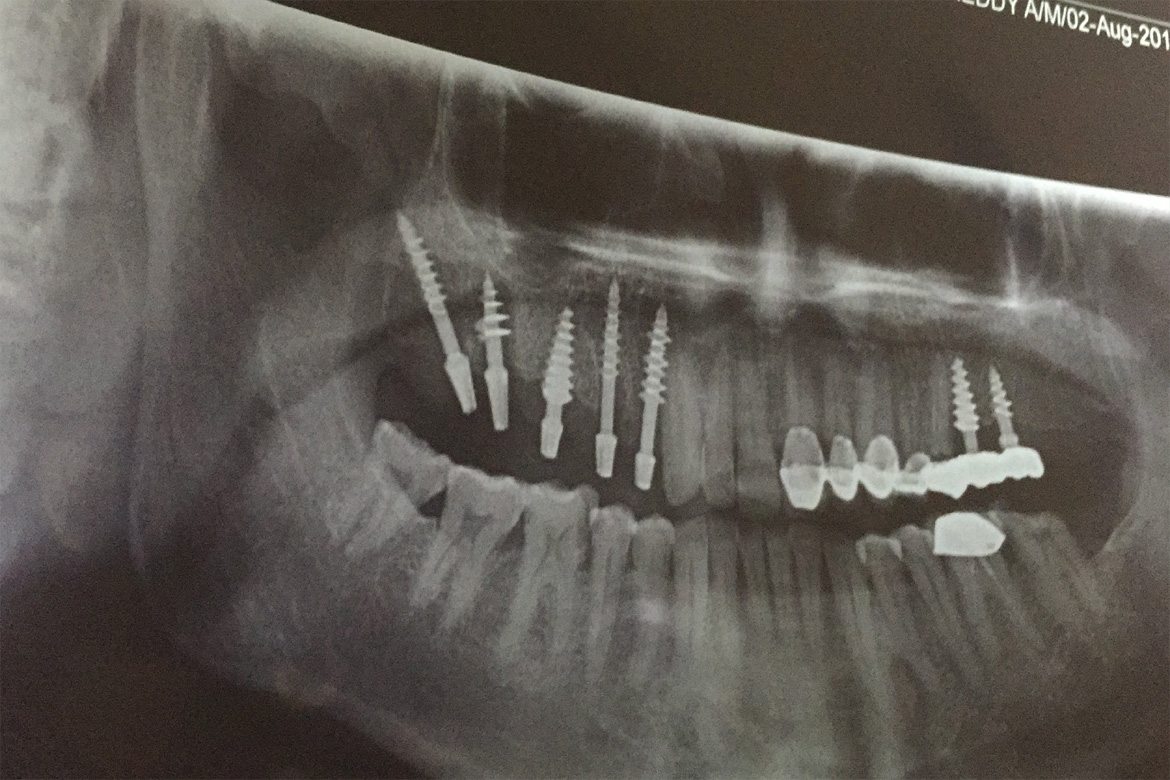

A Dental implant is a titanium post that is placed in your jaw bone which interfaces,integrates or interlocks (as in BASAL IMPLANTS) to provide a strong and secure foundation that replaces your missing teeth permanently.

They preserve the natural bone and also help stimulate fresh bone growth.